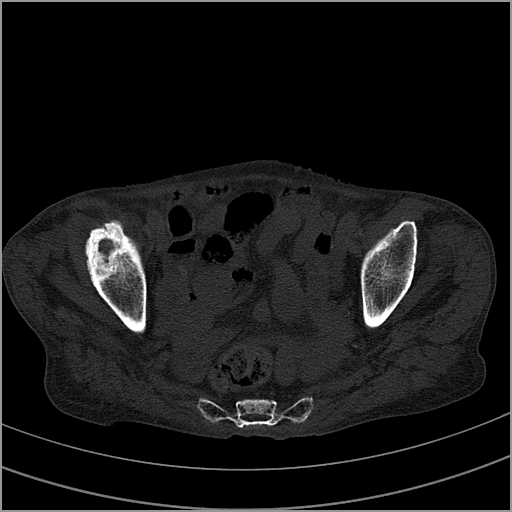

以下是引用老爱克斯新网客在2009-2-3 19:42:00的发言:[br]右侧髋臼及右侧股骨头可见明显骨质破坏,以溶骨性破坏为主,无明显硬化,髋关节间隙变窄,周围软组织明显肿胀,密度不均,脂肪间隙消失。[br] 诊断:右侧髋关节感染性病变,右侧髋关节结核的可能大。[br] 鉴别诊断:1.股骨头缺血坏死,单纯股骨头缺血坏死病例不会累积髋臼骨破坏。2。退行性关节炎,以骨质增生为主,伴有关节面硬化,骨质破坏呈多发小囊状破坏为主,其周围可见硬化环。3.股骨头缺血坏死晚期(第四期)骨质破坏可伴髋关节退行性变,可有骨质增生,但此时骨破坏以股骨头破坏为主,不应该伴有髋臼骨质破坏,因为股骨头的骨破坏是因血运中断,而没有髋臼的血运中断,又没有细菌的感染,怎么能造成髋臼的骨破坏呢。